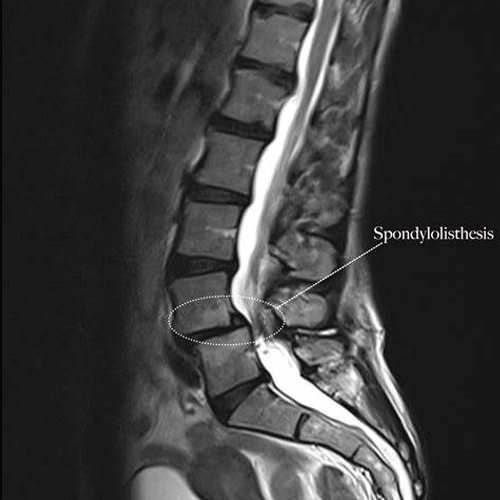

What is Spondylolisthesis?

Spondylolisthesis happens when one of the bones in your spine (vertebrae) slips out of place, usually in the lower back. This can cause:

Using MRI, CT scans, and X-rays to determine the grade and type of slippage.